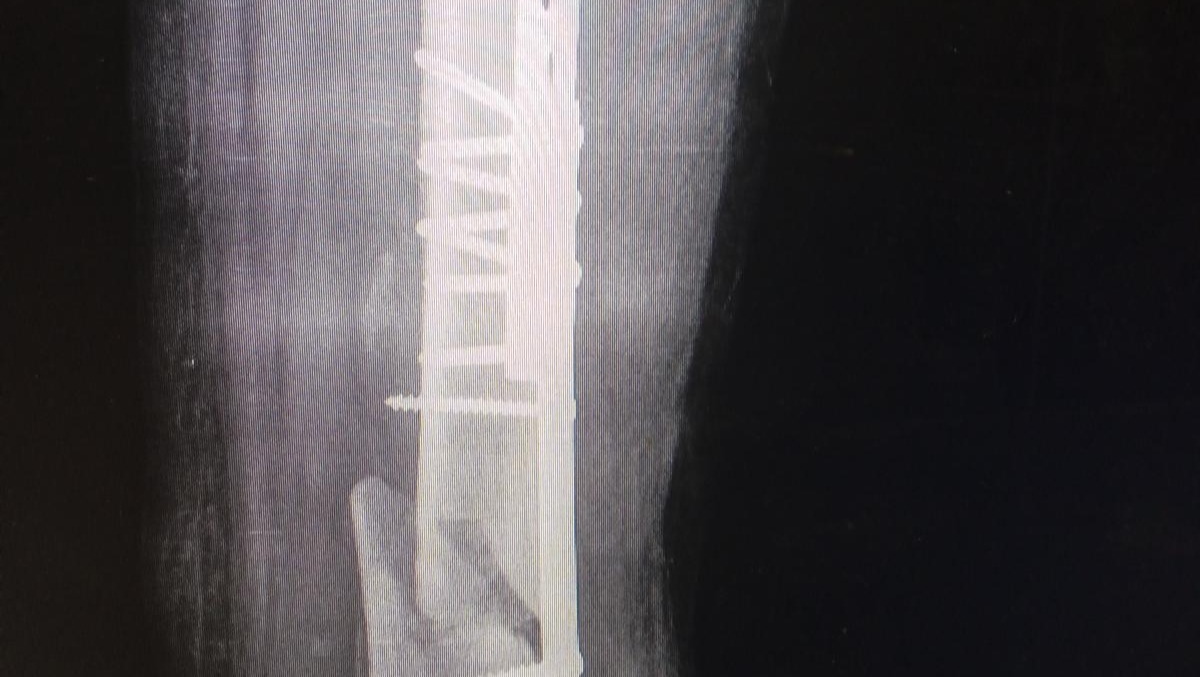

The First X-ray Of The Two Broken Bones

The External Fixation..

An X-ray Of The External Fixation..

The surgery he did in February was because his leg got infected from the inside. And the last surgery he did in April was for the second broken bone, the doctors had put internal pins in the bone.